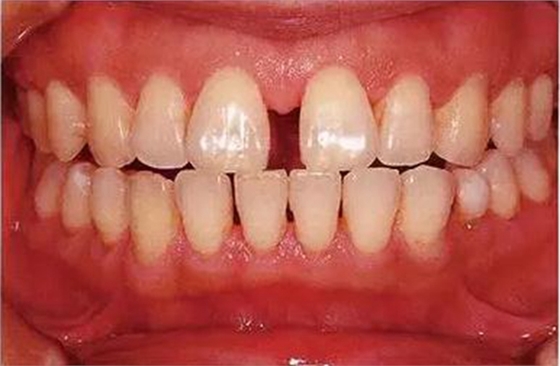

●參考病例① 35歲女性

35歲女性。妊娠4個(gè)月。過(guò)去雖然接受過(guò)刷牙指導(dǎo),但菌斑控制狀態(tài)依然不理想?;颊哂邪l(fā)現(xiàn)自己刷牙時(shí)牙齦出血。

●參考病例② 25歲女性

25歲女性。菌斑控制狀態(tài)不好。齦溝除磨牙處外全在3mm以下,X光照片上左上、右下、左下的第一磨牙上有垂直性骨吸收。這個(gè)病例是參考病例①10年前的狀態(tài),是典型的侵襲性牙周炎局部型。